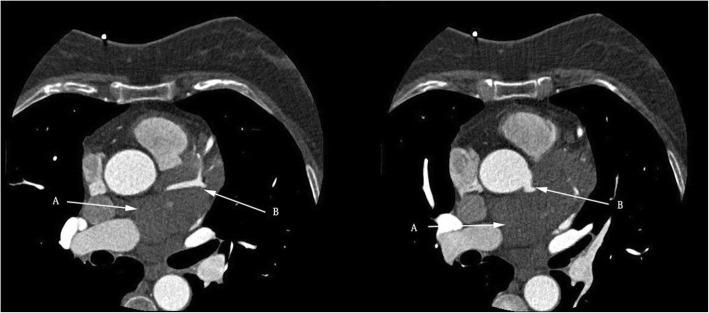

An asymptomatic 56-year-old woman was hospitalized due to a heart mass found by chest computed tomography (CT) during her annual physical examination. Coronary computed tomography angiography (CTA) disclosed a tumorous lesion, located in the left atrial roof and extended to the posterior wall of the aortic root and surrounding the left main coronary artery. However, there was no communicating branches between the hemangioma and coronary artery and no coronary artery stenosis. The tumor was excised with low-frequency electrocautery under cardiopulmonary bypass. The histopathological examination indicated the mass a cavernous hemangioma. The patient was discharged with an uneventful recovery.

一名56岁无症状女性因年度体检时胸部计算机断层扫描(CT)发现心脏肿物而住院。冠状动脉计算机断层扫描血管造影(CTA)显示一个肿瘤性病变,位于左心房顶部,延伸至主动脉根部后壁并包绕左冠状动脉主干。然而,血管瘤与冠状动脉之间无交通支,也无冠状动脉狭窄。在体外循环下用低频电灼切除肿瘤。组织病理学检查显示肿物为海绵状血管瘤。患者康复顺利出院。